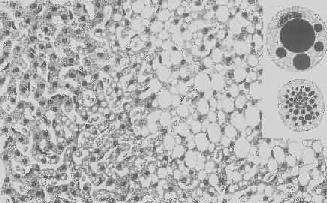

肝淀粉样变

图1-22 肝淀粉样变

淀粉样物质呈均质状,沉着于窦内皮下,肝细胞索受压萎缩

形态学:轻度肝脂肪变性时,肝肉眼观可无明显改变,或仅轻微黄染。如脂仿变性比较显著和广泛,则肝增大,色变黄,触之质如泥块并有油腻感。镜下,肝细胞内的脂肪空泡较小,起初多见于核的周围,以后变大,较密集散布于整个胞浆中,严重时可融合为一个大空泡,将细胞核挤向胞膜下,状似脂肪细胞(图1-18)。脂肪变性在肝小叶中的分布与其病因有一定的关系,例如肝淤血时,小叶中央区缺氧较重,故脂肪变性首先在此处发生。但长期淤血后,小叶中央区的肝细胞大多萎缩、变性或消失,于是小叶周边区肝细胞也因缺氧而发生脂肪变性。磷中毒时,肝细胞脂肪变性则主要发生于小叶周边区,这可能是由于此区肝细胞对磷中毒更为敏感的缘故。

肝细胞脂肪变性

图1-18 肝细胞脂肪变性

肝细胞胞浆内出现大小不等的脂肪空泡;右上角为饿酸染色的脂肪细胞, 脂滴染成黑色

5.淀粉样变性 组织内有淀粉样物质沉积称为淀粉样变性(amyloid degeneration,amyloidosis)。淀粉样物质为一种结合粘多糖的蛋白质,遇碘时被染成赤褐色,再加以硫酸则呈蓝色,与淀粉遇碘时的反应相似,故称之为淀粉样物质。此物质常浸润于细胞间或沉积于小血管的基底膜下,或沿网状纤维支架分布(图1-22)。淀粉样物质在HE染色切片中为淡红色均质状,电镜下则为纤细的丝状。